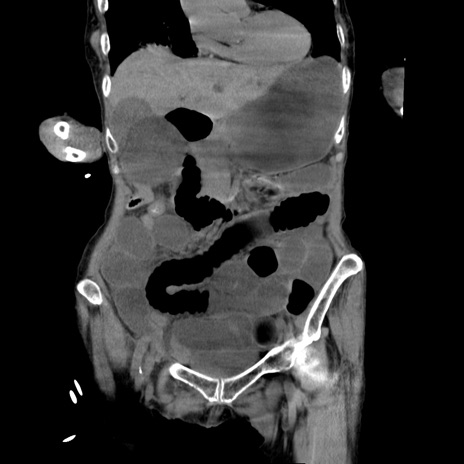

症例27(冠状断像)

【症例】80歳代女性

【主訴】嘔吐、腹痛

【現病歴】数時間前より嘔吐あり。心窩部痛出現し、徐々に右下腹痛あり。その後も数回嘔吐あり救急搬送となる。

【身体所見】腹部は膨隆しているが軟らかく圧痛なし。腸雑音はやや亢進。

【データ】WBC 12000、CRP 19.05